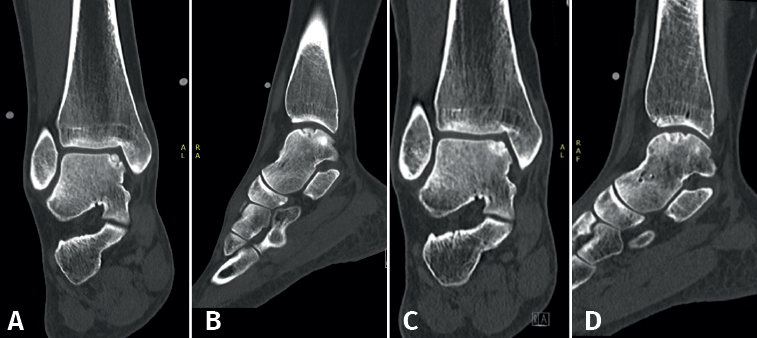

Las lesiones pueden caracterizarse por su localización, morfología y tamaño. La localización puede describirse utilizando un esquema anatómico del astrágalo de 9 cuadrículas, como el descrito por Raikin et al., que se muestra en la Figura 1(14). La morfología de una OLT puede describirse como crateriforme, quística o fragmentaria (Figura 2)(4,15,16). El tamaño de la lesión debe indicarse en el plano anteroposterior, en el plano medial-lateral y en profundidad, lo que permite calcular la superficie y el volumen de la lesión(4). Sin embargo, no hay consenso sobre la morfología de las OLT y, aunque existen sistemas de clasificación radiológica de las OLT, carecen de validación y utilizan una terminología incongruente. Además, los métodos de medición del tamaño de las lesiones varían, lo que contribuye aún más a la incongruencia en la caracterización de las lesiones en la literatura(15).

Figura 2. Tipos de morfologías de las lesiones osteocondrales del astrágalo observados en tomografía computarizada en vista coronal y sagital. A: crateriforme; B: quística; C: fragmentaria.